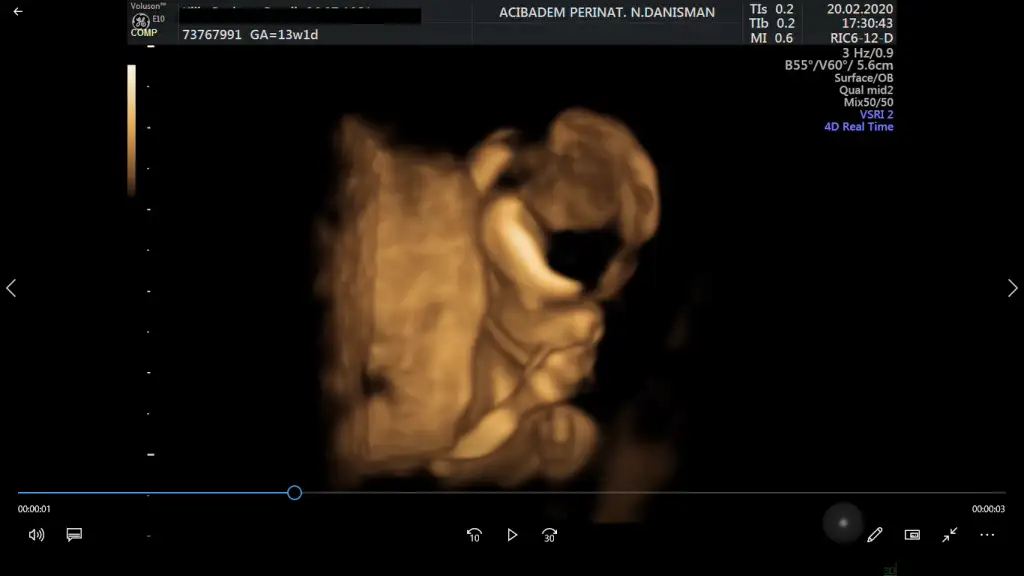

Yaaaa annesi neden dertli diyorsun ki? Dün doktorum bana "Filozof olacak bu" dedi. Benimki de sürekli düşünüyor. Şimdi doktorun verdiği usg videolarını izliyorum. Aman Allah'ım içimde resmen bir dünya var! Allah bize nasıl bir şey bahşetmiş, kafayı yememek elde değil. Minyatür insan!

Eki Görüntüle 2594047 Eki Görüntüle 2594048

Bu güzellik doktorunun dediği gibi tam bir Filozof bir eliyle çenesini tutmuş bir elini yumuruk yapmış..Maşallah maşallah kuzuya Allah esirgesin..

Sagol canim benim, amin 😍 Burada odak noktasi beyin idi. Videodan rastgele ben kestim goruntuyu. 🤪